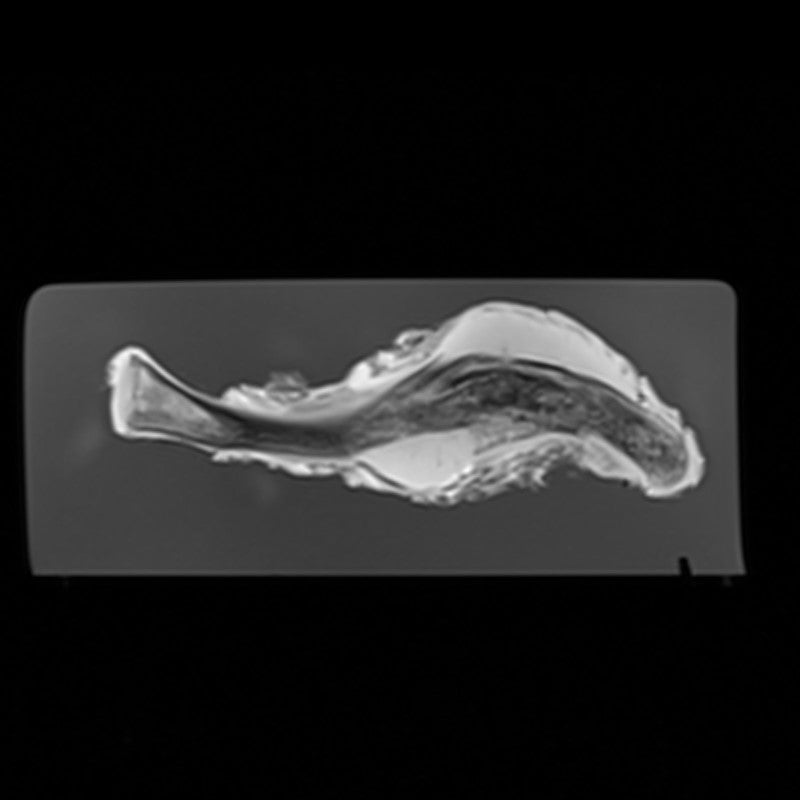

Rib - Chondrosarcoma